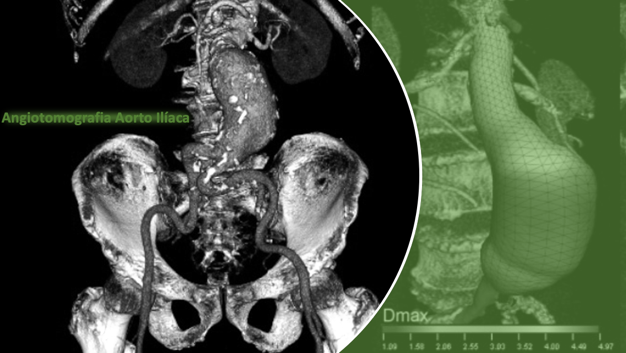

Outros métodos complementares de exames de imagem como tomografia computadorizada e até métodos mais invasivos como as arteriografias podem ser feitos para melhor avaliar a doença e/ou melhor direcionar a sua programação cirúrgica.

O risco de ruptura do aneurisma, complicação gravíssima da doença, está diretamente associado ao seu diâmetro transverso, a velocidade de crescimento, doenças cardíacas e pulmonares associadas, mas nem sempre o tratamento cirúrgico será necessário, porém quando indicado, utiliza-se preferencialmente técnicas endovasculares menos invasivas como a colocação de endopróteses ou embolizações.